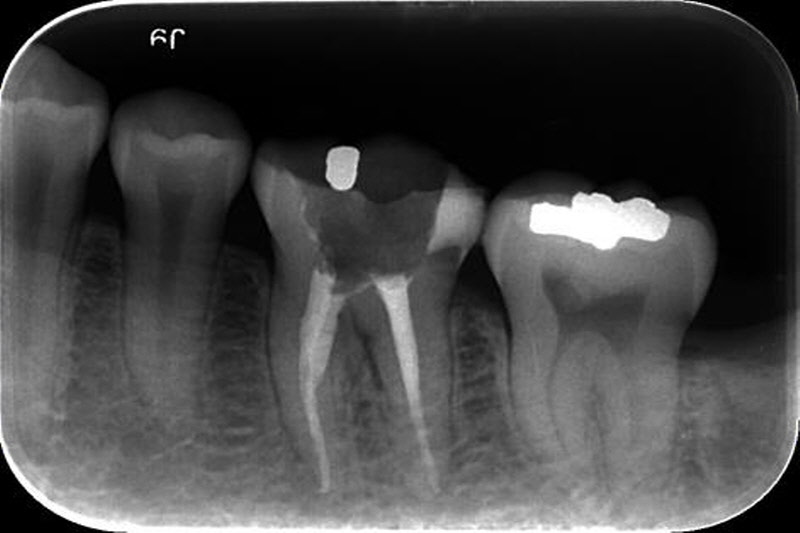

좌측의 초기부터 점점 진행되는 충치의 사례입니다. 제일 좌측은 치료받지 않고 두어도 무관한 정도이지만 가장 우측은 발치를 시행해야 하는 정도로 진행되어 있습니다. 충치는 명쾌하게 단계를 자를 수 있는 병이 아닌 점진적 진행으로 나타나므로 같은 정도의 충치라도 많은 변수를 고려해야 합니다. 의사마다 치료 방법과 방향이 다른 이유입니다. 각자의 경험과 생각하는 바, 앞으로의 예후와 환자의 조건들을 총 취합해서 평가해야 하니 같은 경우는 드물게 됩니다 .

치아우식증의 치료는 진행 단계에 따라 다르지만 원리는 비슷합니다. 치아우식증에 이환된 부위를 제거하고 그 부위를 채워 회복하며 나머지 남아있는 자기 치아 부위를 파절이나 손상으로부터 보호하는 것입니다. 충치를 치료하는데 있어서는 두 가지를 생각해야 합니다. 채워 넣는 부분의 수명과 남아있는 나머지 자신의 치아부위의 수명을 동시에 고려해야 합니다. 흔히들 채워 넣는 수복물의 수명만 많이 고려하지만, 결국 그 수복물을 유지해주는 것은 잔존 치아 부분입니다. 잔존 치아 부위에 무리를 가하는 수복물이라면 치료 수명은 오래가지 못할 것입니다.

가끔은 충치가 너무 진행이 되어 신경에 문제가 되는 경우도 있는데 이런 경우는 신경치료를 먼저 시행하고 그 다음 크라운으로 치아를 보호해 주는 방식으로 치료 되어야 합니다. 크라운의 재료로는 금과 도자기를 들 수 있습니다. 금 크라운은 씹는 충격 등에 강하고 치아를 삭제하는 양을 조금 줄일 수 있으며, 향후 생기는 변화에 적응되는 능력이 뛰어납니다. 단점으로는 금색이므로 예쁜 모습이 필요한 부위에 적용할 수 없으며, 열의 전달이 빨라 씌운 후 경우에 따라 당분간 좀 더 시릴 수 있습니다. 시간이 지나면 시린 부분은 많이 감소하게 됩니다.

필요시 신경치료를 동반하기도 한다.